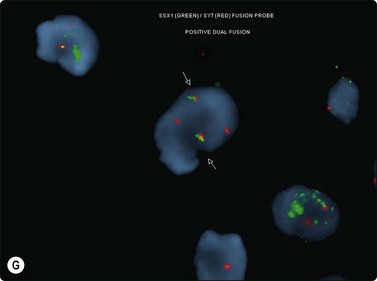

The most common sarcomas of this site include malignant fibrous histiocytoma and liposarcoma.131,132 Synovial sarcoma is well described.133 We have seen a single case of monophasic synovial sarcoma of mediastinum diagnosed on transoesophageal EUS FNB by the demonstration of SYT-SSX fusion transcripts by FISH on cell blocks, indicating X:18 translocation (all material shown here is courtesy of Dr. Anita Soma, PathWest QE II AP). (Fig. 9.10) The patient was a 45-year-old male with an 11-cm mass adjacent to the lower oesophagus, displacing the heart. Smears showed a rather bland spindle cell population but with mitotic activity. The cell block immunohistochemistry was negative for cytokeratins, CD117 and smooth muscle markers, making leiomyosarcoma and GIST unlikely. The tumor did show positive staining for CD99, BCL2 and CD34, raising the possibility of solitary fibrous tumor or synovial sarcoma. An SYT-SSX1 fusion transcript was detected by reverse transcriptase PCR, reinforcing the FISH cytogenetics. No other diagnostic procedures were undertaken (Fig 9.10).

Fig. 9.10 Synovial sarcoma

(A) Large infiltrative mass posterior to heart (Thoracic CT); (B) Loose fascicle of spindle cells including small blood vessels. Background of bare tumor nuclei (H&E, LP); (C) Loose cluster of bland spindle cells but with mitotic activity (H&E, HP); (D) Cell block, small spindle tumor cells with non-specific features (H&E, HP);(E) FISH on cell block, breakapart probe for SYT showing positive disruption of red-green-yellow components (FISH, HP); (F) FISH on cell block, fusion probe for SSX2 (green) and SYT (red) probes showing positive fusion of green and red components. (FISH, HP); (G) FISH on cell block, fusion probe for SSX2 (green) and SYT (red) probes showing positive fusion of green and red components (FISH, HP).